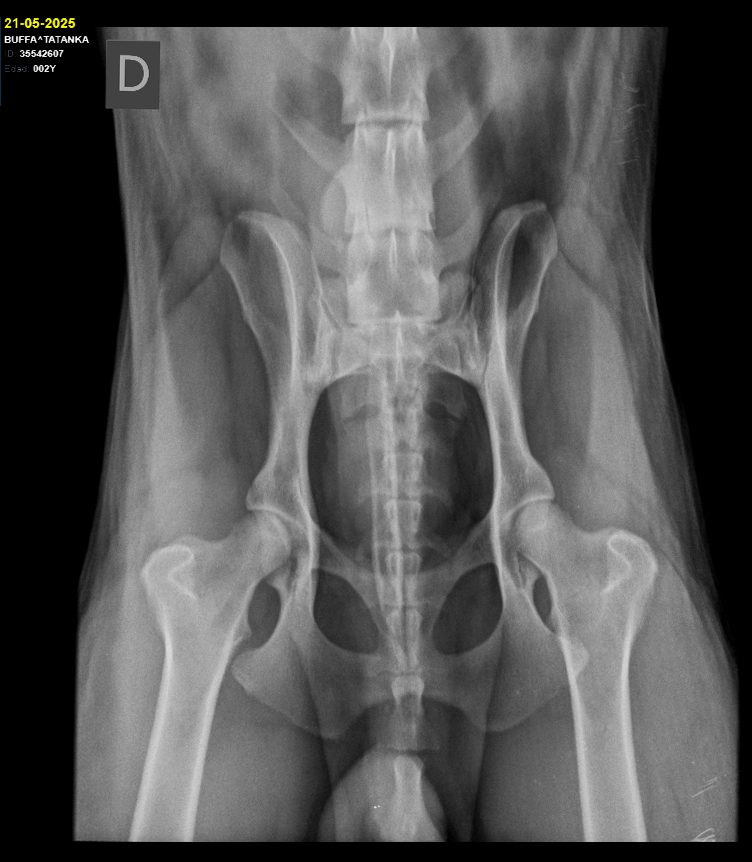

Sex: Female

Fecha de nacimiento: 01/08/2023

Coat: Long

Hips and elbows:

HD A/A ED 0/0

MDR1 +/+ DM N/N

Height: 63cm

Weight: 38kg

Makeba is named in honor of Miriam Makeba, South African singer, global icon of the fight for human rights.

She is the reflection of her father Rixon, a strong, robust but feminine female... with a very even-tempered character, self-confident, sociable and affectionate with everyone, calm but mischievous when no one is looking. Despite her remarkable size, she is very subtle and gentle in her manner, and has a very unusual wisdom in a young dog.